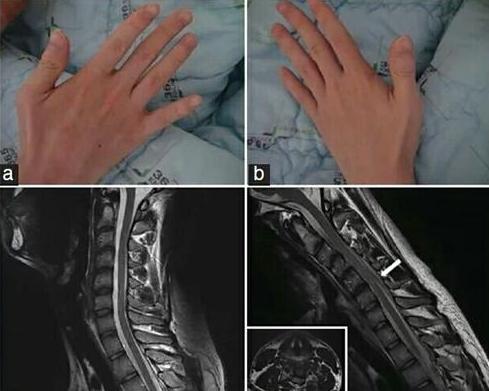

几个月前接诊了一例罕见的平山病患者,孩子患有伸指障碍伴伸指时手抖震颤、右手消瘦无力握不住东西,双手外观呈鸡爪状。在经过一段时间的颈托佩戴后,孩子妈妈说病人近来手抖情况明显好转。

平山病,手部外形特征有点像我们说的爪形手,手背部的肌肉叫做股间肌,是平山病最容易受损的部位。手背肌肉萎缩会出现明显的骨间沟状形态。一旦手指伸不直,呈爪形手,且前臂呈一个斜坡样的萎缩也要注意平山病。

医学影像检查,常表现为颈椎X光片检查无异常,但屈曲位颈椎核磁共振检查会有特殊发现,硬脊膜向前移位并压迫脊髓且伴有血管留空信号。同时,神经肌电图显示脊髓前角损害。